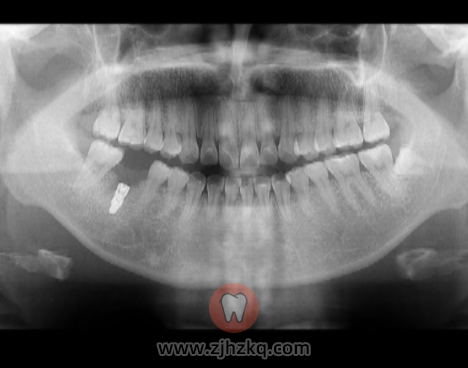

支付宝上预约周医生的诊,挂号费25元。取号后6楼排队等待叫号进入诊室,进入后周医生让我先去做一个ct(cbct3)和全景片,以便确定是否具备直接种植条件(需要测量槽骨高度),两项共花费215元。

时隔四月,我终于过来进行下一阶段的治疗了,本来该6月份过来的,因为私事拖到7月份,这次过来先是挂号、然后医生让做了一个全景CT,通过图片,医生说我骨头长得不错,愈合很好,甚至骨头长得有点多需要磨掉一点,接着就打麻药进行磨骨、安装基台愈合帽(不知道这样说是否准确)、伤口缝合。